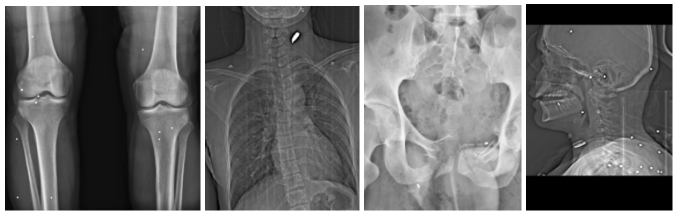

در این گزارش، فکتنامه و گاردین ۷۸ تصویر پزشکی را که از یک بیمارستان در یکی از شهرهای بزرگ ایران به طور مستقل تایید و بررسی کردهاند. تصاویر، مربوط به ۶۴ فرد آسیبدیده است. این تصاویر شامل ۲۹ عکس از نوع X-Ray و ۴۷ مورد تصویر CT و دو مورد CTA (مربوط به یک مجروح) است که همراه با اطلاعاتی مثل زمان دقیق تصویربرداری، ناحیه یا نواحی تحت بررسی، نام، جنسیت و در برخی موارد وضعیت سنی بیمار در اختیار فکتنامه قرار گرفته است. این تصاویر همچنین حاوی دادههایی درباره مراکز درمانی و مشخصات بیماران بودهاند که بهصورت کامل نزد تیم تحقیق محفوظ ماندهاند.

دادههای این تحقیق شامل ۷۸ تصویر پزشکی از نوع اشعه ایکس، سیتیاسکن و سیتیآنژیوگرافی است که به ۶۴ بیمار مجزا تعلق دارد. برخی از این موارد بیش از یک تصویر دارند که در مواردی در زمانهای متفاوت و در جریان روند تشخیصی یا درمانی ثبت شدهاند. از کل ۶۴ مورد موجود، ۵۹ مورد بهدلیل وجود شواهد رادیولوژیک روشن از اصابت گلوله یا ساچمه وارد تحلیل نهایی شدهاند. پنج مورد دیگر، پس از بازبینی دقیق، بهدلیل فقدان هرگونه نشانه قابل اتکا از برخورد پرتابه یا آسیب ناشی از سلاح گرم، بهصورت نظاممند از تحلیل آماری کنار گذاشته شدهاند.

تصاویر رادیولوژی نشان میدهد که در این مجموعه، دو الگوی غالب شلیک قابل تفکیک است: آسیبهای ناشی از ساچمههای شاتگان و آسیبهای ناشی از گلولههای پرسرعت کالیبر ۷٫۶۲. تشخیص این موارد بر اساس اندازه، شکل، تعداد، نحوه پراکندگی، تغییر شکل فلزی و مسیر احتمالی حرکت پرتابه در بدن، از تصاویر واضح است.

در آسیبهای منتسب به گلولههای پرسرعت ۷٫۶۲ میلیمتری تصاویر وجود یک جسم فلزی بزرگتر، اغلب تغییر شکل یافته، را نشان میدهند که در برخی موارد با شکستگیهای چندتکه استخوان و تخریب گسترده بافت نرم همراه است. در چند پرونده، مسیر تقریبی حرکت گلوله از روی شکستگیهای استخوانی، پراکندگی قطعات فلزی و جهت آسیب قابل بازسازی نسبی بوده است. تغییر شکل پرتابه پس از برخورد با استخوان و توقف آن در بافت، در برخی موارد بهعنوان یافته سازگار با گلولههای تمامفلزی (FMJ) پرسرعت توصیف شده است.

در ۱۰ کیس، یافتههای تصویری با الگوی سازگار با اصابت گلولههای کالیبر ۳۹×۷٫۶۲ میلیمتری توصیف شده است؛ مهماتی که معمولا با سلاحهای خانواده تفنگهای تهاجمی کلاشنیکف شلیک میشوند. در این موارد، تصاویر وجود یک پرتابه فلزی بزرگتر، گاه تغییر شکل یافته، را نشان میدهند که با نفوذ عمیق و تخریب گسترده استخوان و بافت نرم همراه بوده است. در چند پرونده، گلوله پس از برخورد با استخوان دچار تغییر شکل شده و در بدن باقی مانده است، بدون آنکه مسیر خروجی مشخصی دیده شود؛ الگویی که با مهمات تمامفلزی پرسرعت همخوانی دارد.

از نظر الگوی آسیب، شکستگیهای خردشونده در استخوانهای ران، لگن و بازو بهطور تکرارشونده مشاهده شدهاند. در چند مورد، آسیب قفسه سینه با پنوموتوراکس (هواجنبی) و نیاز به مداخله اورژانسی همراه بوده است. در یک پرونده، گلوله در ناحیه گردن دیده شده و با جابجایی نای و نشانههای تورم و خونریزی سازگار بوده است؛ وضعیتی که پزشک آن را با احتمال آسیب به عروق بزرگ و خطر سکته یا مرگ مرتبط دانسته است. در یک مورد دیگر، درگیری مغزی با ریسک بسیار بالای مرگ توصیف شده است. همچنین در چند مورد، احتمال آسیب به شریان فمورال (سرخرنگ رانی) و خطر خونریزی تهدیدکننده حیات مطرح شده است.

در مجموع، موارد منتسب به گلولههای ۷٫۶۲×۳۹ میلیمتری از نظر شدت تخریب بافتی و استخوانی، بیشترین پتانسیل مرگآوری را در این مجموعه نشان میدهند. انرژی بالاتر و مسیر نفوذ متمرکز این مهمات، در صورت درگیری اندامهای حیاتی یا عروق بزرگ، با خطر مرگ سریع یا ناتوانی شدید پایدار همراه بوده است.